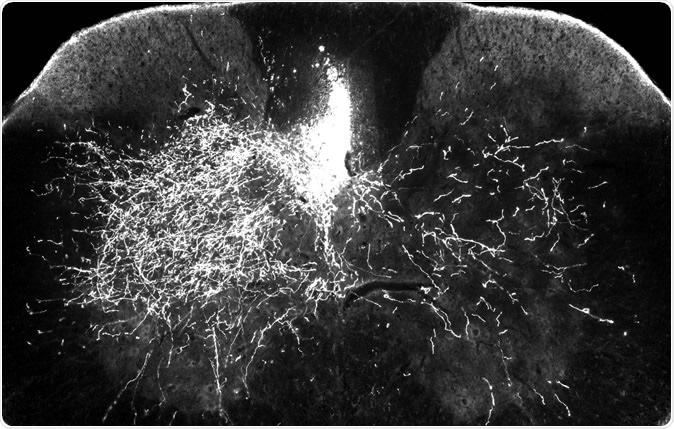

In one of the mouse models for this research, one side of the descending spinal pathway is damaged (above right) while the other side (above left) remains intact. In this image, bright streaks on the right show that in mice treated with gabapentin, descending motor axons are able to sprout to send nerve impulses to the denervated part of the spinal cord – a key step in rebuilding the central nervous system after injury.